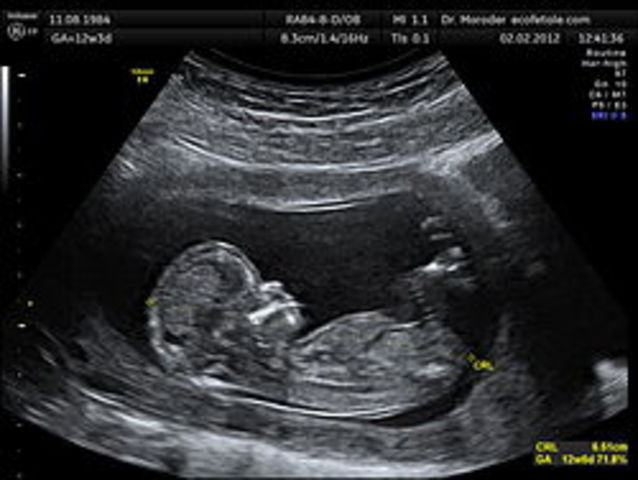

250px crl crown rump lengh 12 weeks ecografia dr. wolfgang moroder

• Semanas 9 a 12

Semanas 9 a 12

Los párpados se cierran y no se vuelven a abrir casi hasta la semana 28

La cara está bien formada

Las extremidades son largas y delgadas

Los genitales aparecen bien diferenciados

Los glóbulos rojos se producen en el hígado

El tamaño de la cabeza corresponde casi a la mitad del tamaño del feto

El feto puede empuñar los dedos

Aparecen los brotes dentarios